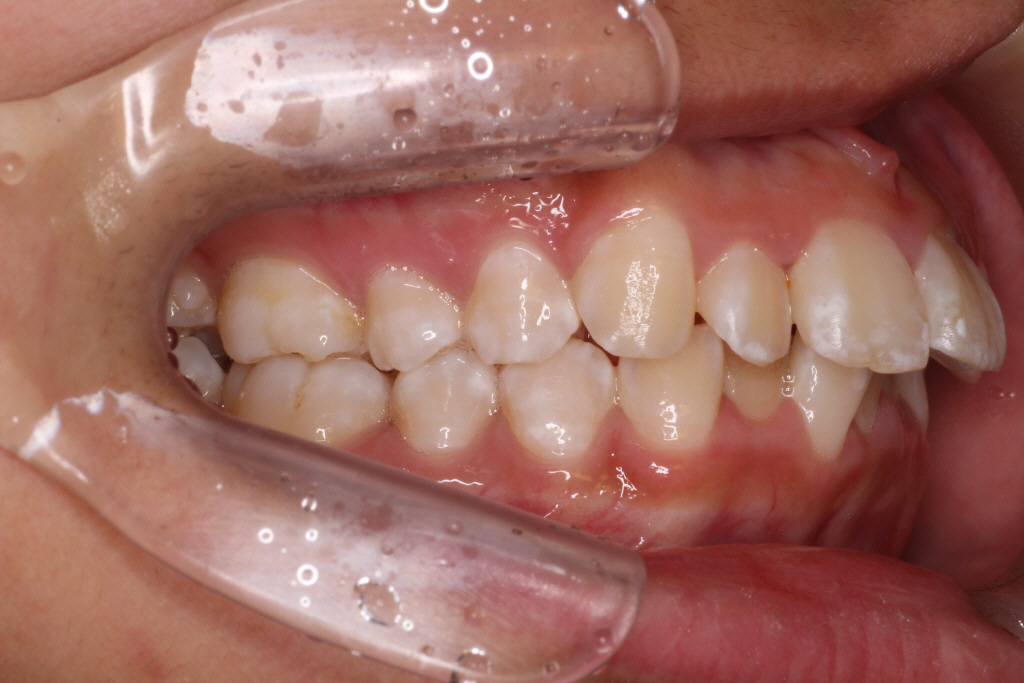

カリエールモーションが終わった時の口腔内写真です。

上の奥歯が後ろに下がったおかげで前歯には隙間ができています。

左の噛み合わせを見ると下の歯と歯の間に上の歯が入り込んでいることがわかります。

1歯対2歯の関係です。

右の噛み合わせを見ると左の噛み合わせより少し多めに奥歯を後ろに下げていることがわかります。

オーバーコレクションといって少し戻ることを想定して多めに動かしておくことを言います。